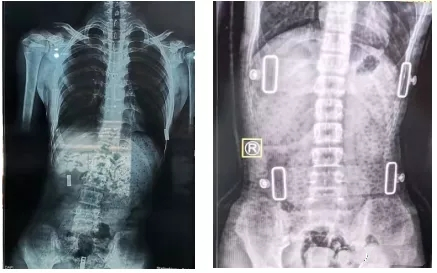

脊柱側彎支具的復查

一般我們認為,支具治療3個月后需要進行復查。復查時需要脊柱全長正側位X線片,同時觀察患者支具佩帶區(qū)域皮膚情況。治療過程中如果患者因生長發(fā)育或其他原因造成支具佩戴有不舒服的感覺,需要重新制作支具。支具一般需要持續(xù)佩戴至生長發(fā)育停止,時間隨孩子就診時間以及生長發(fā)育狀況有所不同。

有時戴了支具后脊柱會反方向傾斜。其實,這是因為一般支具治療會采取一種“過度矯正”的方式,以保證脫下支具后身體的反彈更接近于中心線,而不是向原側彎方向加重。